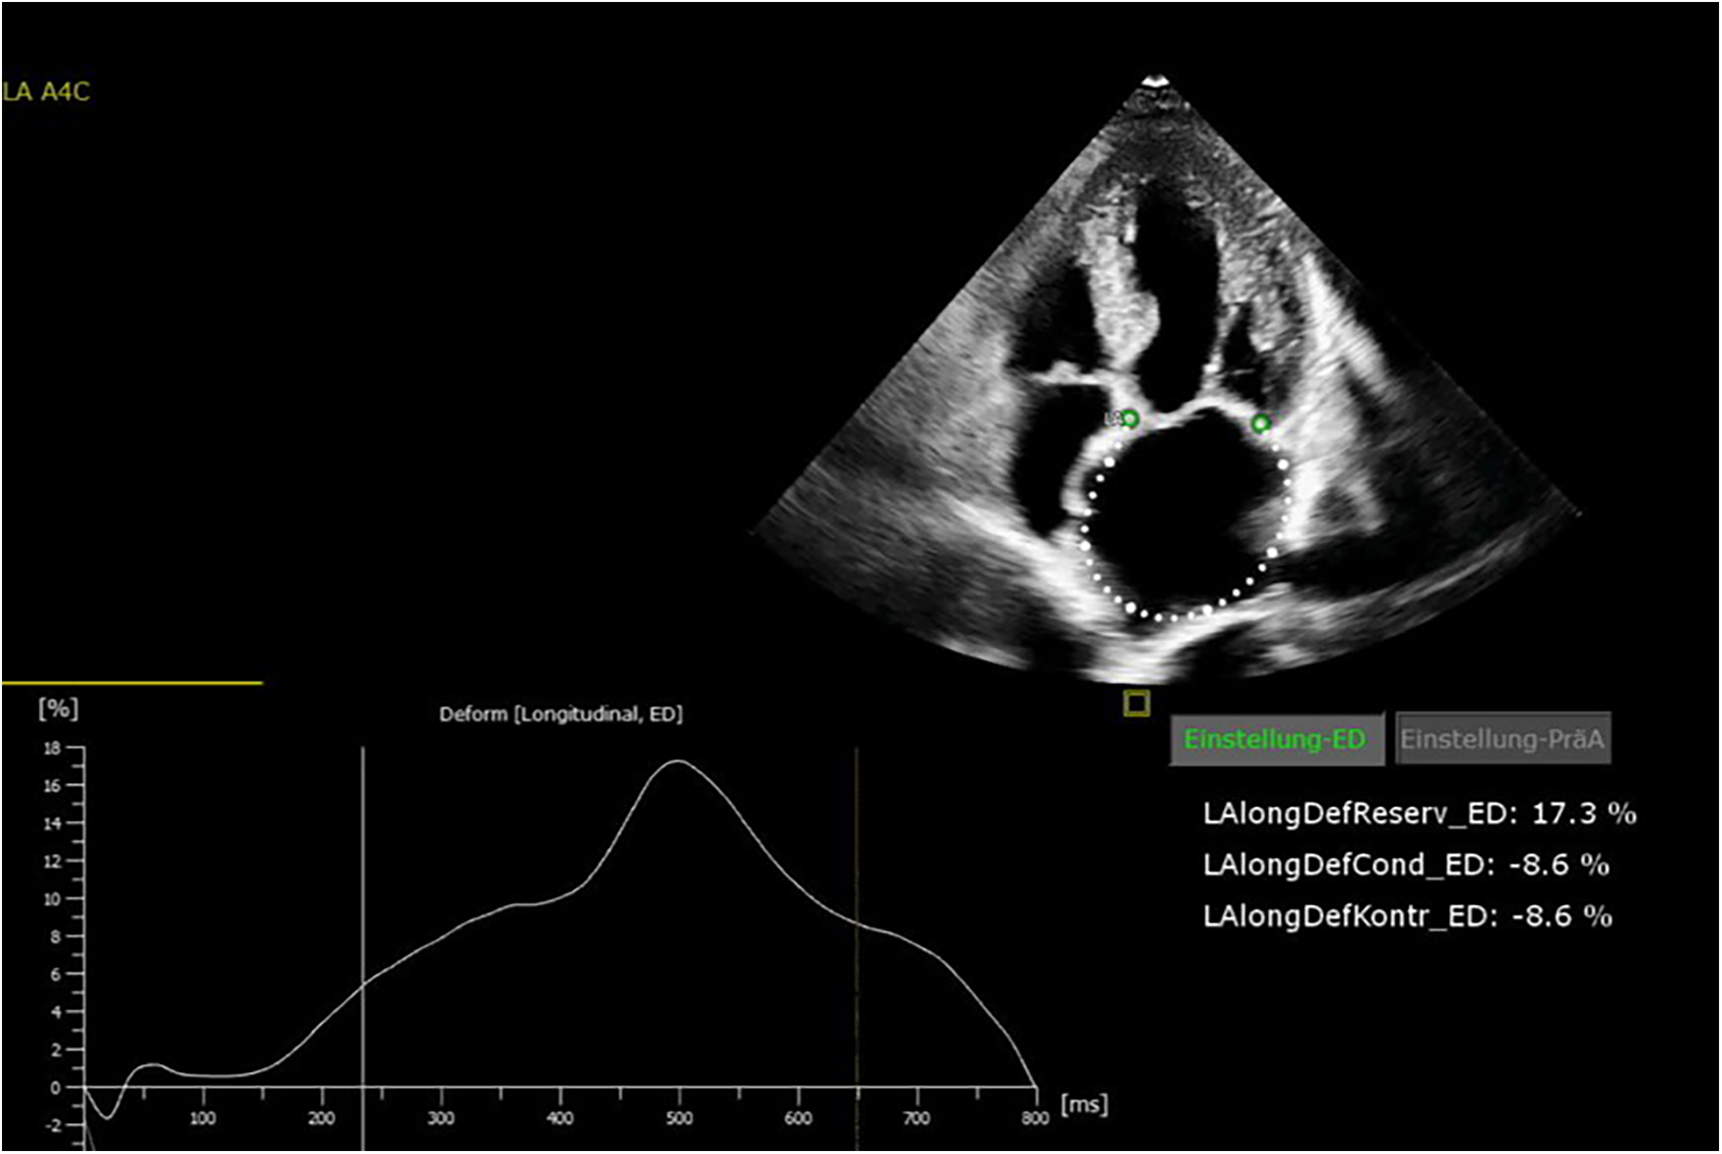

All patients were in AF at the time of preoperative transthoracic echocardiography. The patients were examined by transthoracic echocardiography. After manual tracing of the LA endocardial border, the software Cardiac Performance Analysis (IMAGE-COM, TOMTEC-ARENA, TOMTEC Imaging System GmbH, Unterschleissheim, Germany) automatically tracked the myocardium throughout the cardiac cycle (Figures 2, 3). LA reservoir strain was presented. The same measurements were performed to assess LV strain measurements. The additional echocardiography included an assessment of left ventricular ejection fraction (LVEF), diastolic function, LV hypertrophy, and measurement of LA and left ventricular diameters and volumes. The measurements were according to the current recommendations (21), which are also applicable to strain measurements (22).

Figure 3

Echocardiography showing reduced left atrial (LA) strain values.